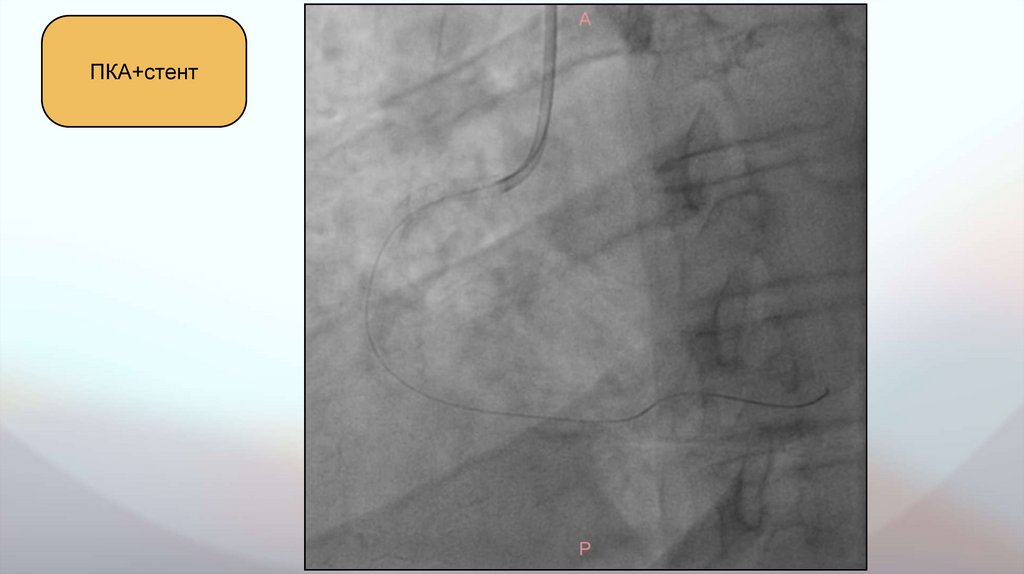

Данные инструментальных исследований. Транслюминальная балконная коронарная

ангиопластика.

Транслюминальная балконная коронарная ангиопластика правой

коронарной артерии:

- выполнен ряд предилатаций в проксимальном сегменте ПКА и

установлен стент Resolute 3,50х18 мм.

ПКА

ПКА+стент